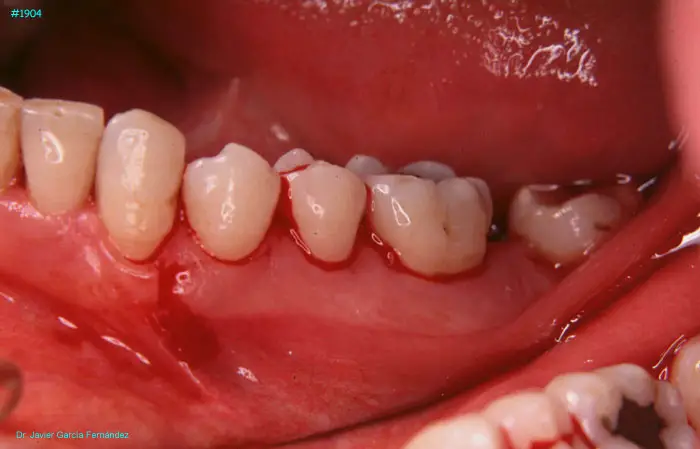

image 50